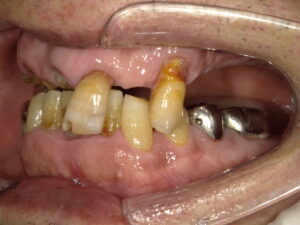

初診時の写真です。

上顎の歯が虫歯でほとんどなくなってしまっています。

上下の歯で噛めるところがありません。

反対側もそうです。

上顎の奥歯は抜いてあるので噛めません。

このような状態では咀嚼ができず、

食べ物を丸飲みするような食事になってしまいます。